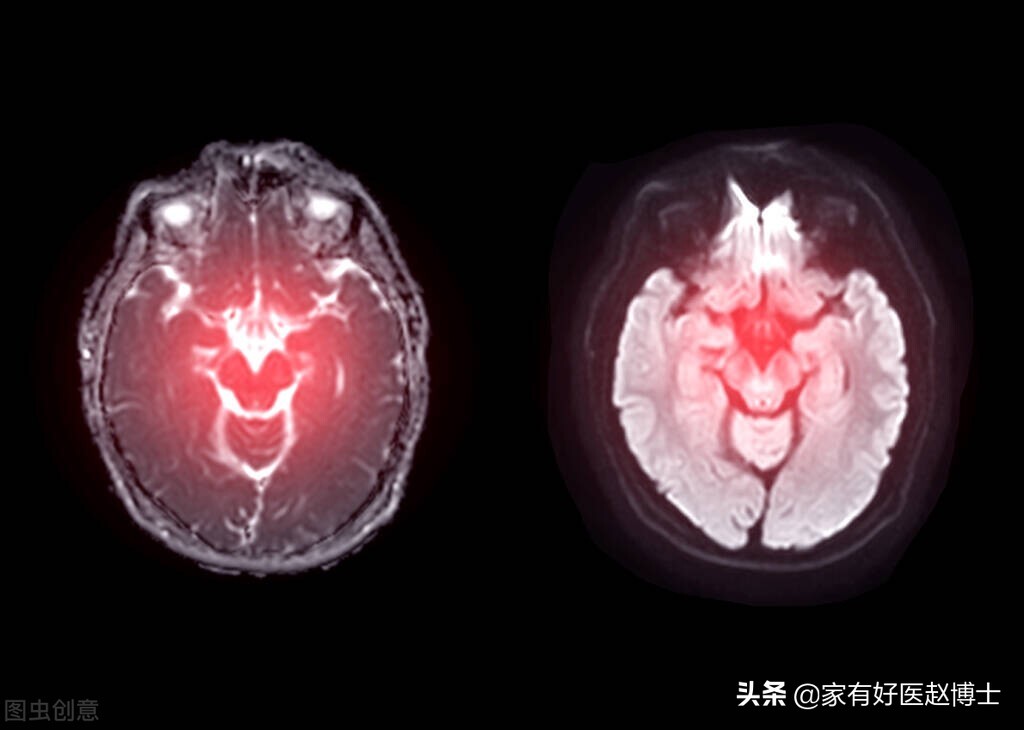

而我们所说的血压“忽高忽低”,医学上的说法其实是“血压变异性增高”。医学研究已经发现,血压变异性的长时间增高不仅与心脏、大脑以及血管的损害有关,还会增加心血管事件和死亡风险。

此外,血压变异性增高还与认知功能障碍、脑卒中等神经系统疾病有密切关联;